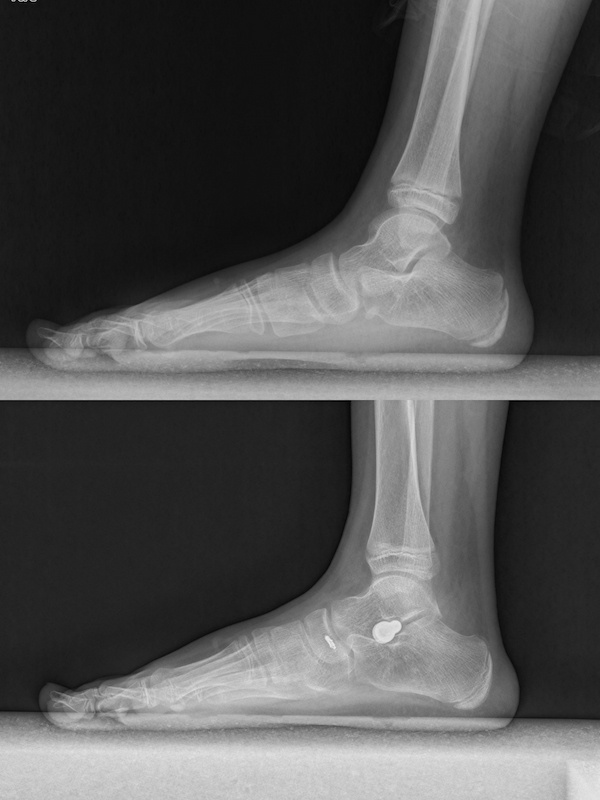

Subtalar joint bracing surgery is a surgical intervention measure for the further treatment of flatfoot that is unresponsive to conservative treatment. It is a minimally invasive treatment method that corrects the deformity of flatfoot by placing a "screw" between the sinus tarsi, talus, and calcaneus, known as a subtalar joint stabilization screw.

Correction of Talus Internal Rotation After Bracing

Correction of Talus Sinking After Bracing

Recovery of the Arch After Bracing Surgery

Correction of Rearfoot Valgus After Bracing Surgery